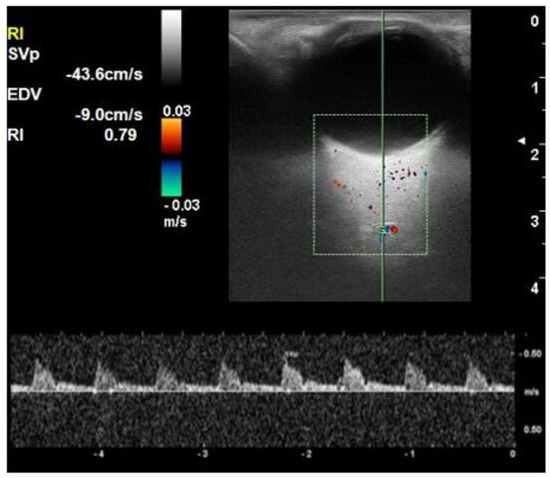

| PSV of central retinal artery (cm/s) | 16.1 ± 1.9 | 15.8 ± 3.1 | 14.2 ± 2.7 | 0.010 |

| EDV of central retinal artery (cm/s) | 5.1 ± 0.7 | 4.8 ± 1.1 | 3.9 ± 1.0 | <0.001 |

| RI of central retinal artery | 0.68 ± 0.03 | 0.69 ± 0.03 | 0.72 ± 0.04 | <0.001 |